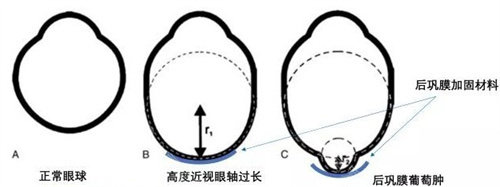

圆锥角膜是一种令人困扰的眼科疾病,而圆锥角膜交联手术为患者带来了希望。